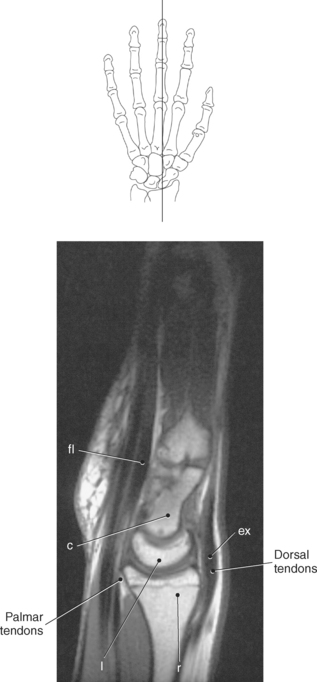

Figure 9.119 Axial, T1-weighted MR scan of wrist with flexor and extensor tendons.

Key: ex, Extensor tendons; c, capitate; h, hamate; fl, flexor tendons; flr, flexor retinaculum; mn, median nerve; tm, trapezium; td, trapezoid.

The numerous muscles of the forearm become tendinous just before the wrist joint. The many tendons located in the wrist can be divided into palmar and dorsal tendon groups (Figures 9.120, A and B and 9.127). The palmar tendon group collectively flexes the fingers and wrist. As this group courses through the carpal tunnel, the tendons appear to be arranged in two discrete rows (Figures 9.118, A and 9.119). The tendons of the dorsal tendon group, spanning the superficial surface of the wrist, are considered the extensors of the fingers and wrist (Figures 9.128 through 9.140).